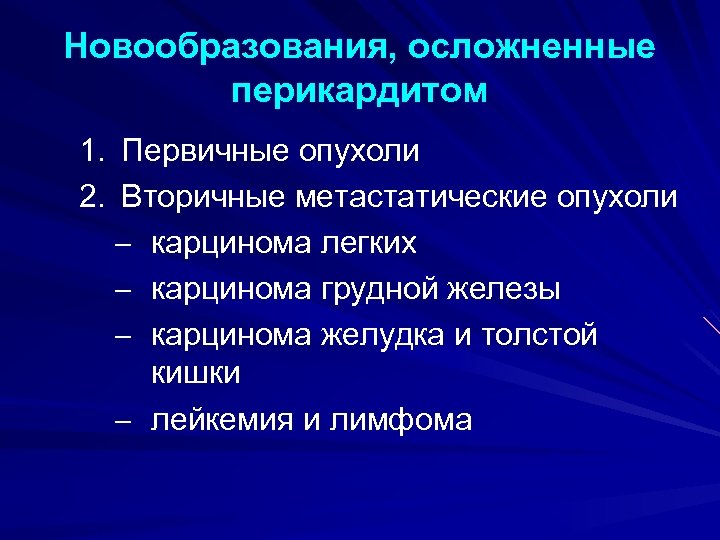

Новообразования, осложненные перикардитом 1. Первичные опухоли 2. Вторичные метастатические опухоли – карцинома легких – карцинома грудной железы – карцинома желудка и толстой кишки – лейкемия и лимфома